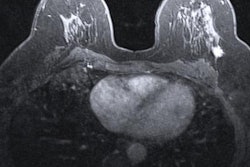

All exams were performed on a 3-tesla MRI scanner using dedicated breast coils with patients in the prone position; 7.5 ml of intravenous gadobutrol (1 mmol/ml) was administered during the exam.

The final diagnoses were obtained from the surgical reports and are shown below.